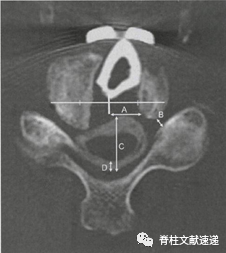

图注:通过术前椎管直径(APD)、脊髓-椎板角(CLA)、椎间孔直径(FD)来预测术后C5神经根麻痹发生。

术前椎管直径(APD)和椎间孔直径(FD)每增加1 mm,发生C5P的几率分别降低69% 和98%;

脊髓-椎板角(CLA)每增加1度,发生C5P的几率就增加43% 。

图注:测量单侧减压宽度(A)、最狭窄部分C4-C5孔前后直径(B)、硬膜囊前后直径(C)和脊髓前移位(D)。

C5神经根麻痹侧减压宽度明显大于非麻痹侧;

较宽且不对称的神经减压,同时存在C4/C5椎间孔狭窄,硬膜扩张容易引起的C5神经根麻痹;

术者应考虑将减压宽度限制在15mm以内,避免不对称减压以减少C5麻痹的发生率;

Kawakami等发现椎间高度增加≥3mm可能会增加C5麻痹的发生率。